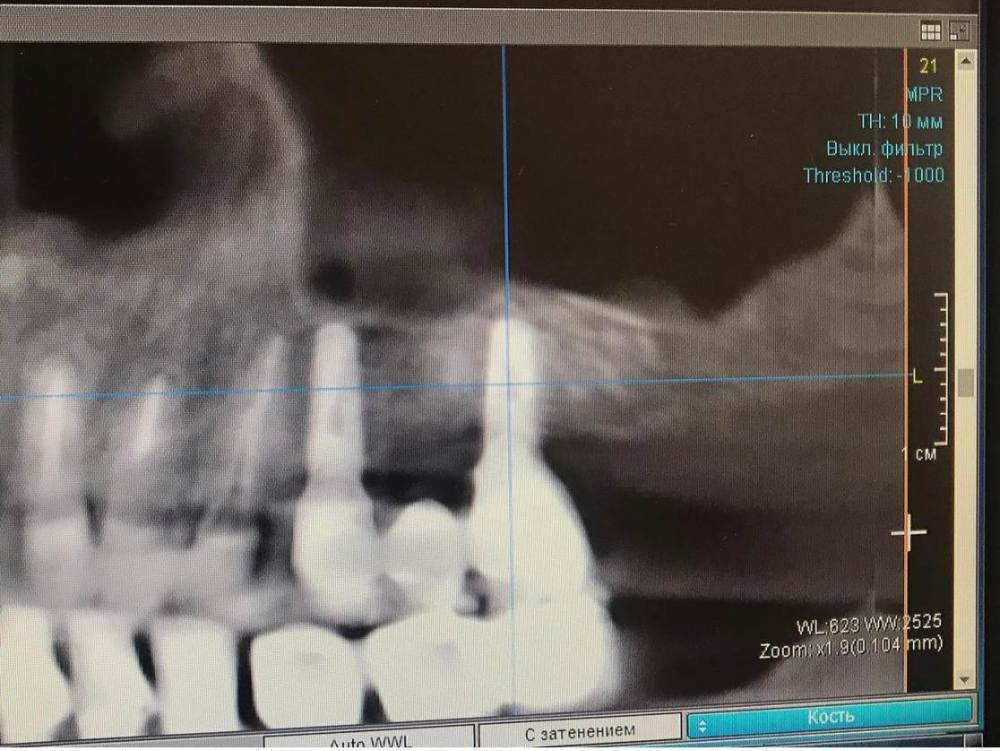

TIGER Опубликовано 18 февраля, 2022 Поделиться Опубликовано 18 февраля, 2022 Приветствую коллеги!Небольшой кейс с удалением кисты и синусом.Произведено :удаление кисты,синус-лифт ,через 4 месяца имплантация,ещё через 4 протезирование 5 1 1 Ссылка на комментарий